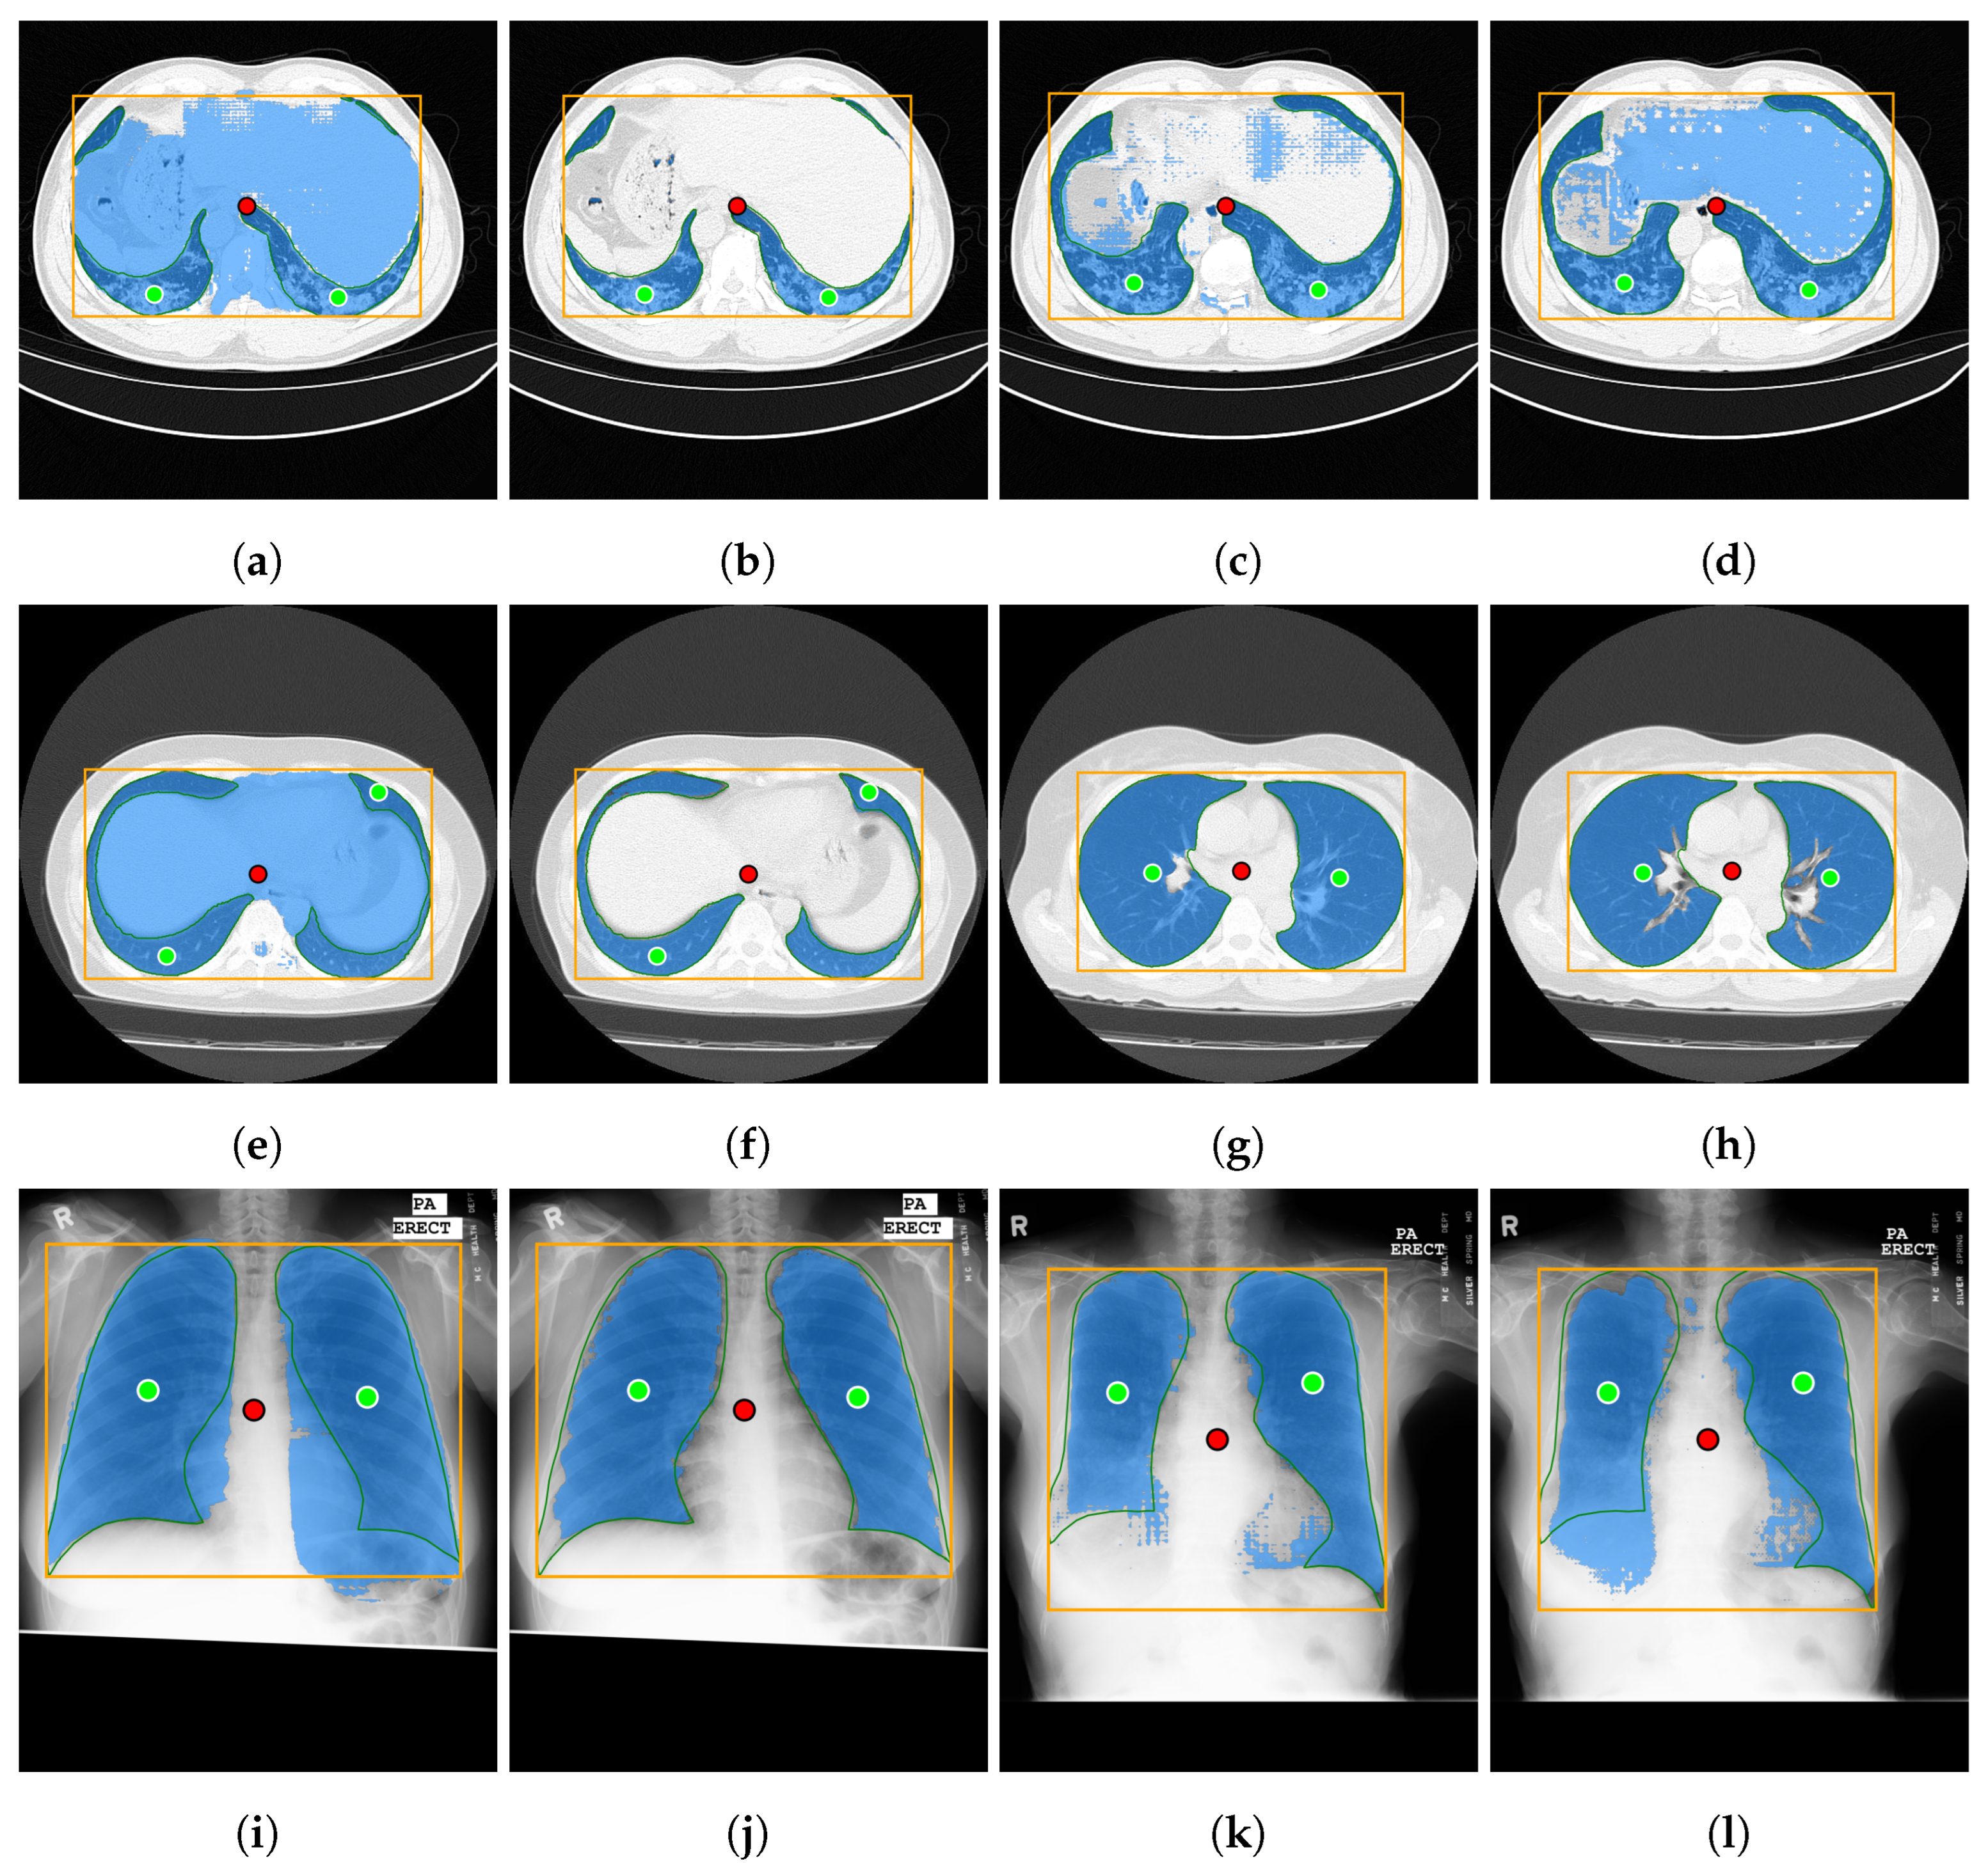

4.2. SAM 2 Video Segmentation for Image Volumes

Figure 12 shows the results of the video segmentation tests described in Section 3.5 in a box plot format. Table 6 shows the exact values of the results. Only the Coronacases and Radiopaedia datasets are shown, as the Montgomery dataset is not structured in volumes. Each Montgomery’s sample is an independent X-ray, with no time relation between them. The X-axis compares the results of SAM and SAM 2 for the Jaccard index and the Dice score. While SAM needs one prompt for each slice to achieve these results, with our proposed technique, SAM 2 only needs one prompt for the whole volume. The Coronacases dataset has 10 volumes and 2156 slices with their corresponding mask. With SAM, we would need 2156 prompts to segment the whole dataset. However, with SAM 2, we only need 10 prompts, one for each volume. The Y-axis shows the values of each metric. Each box plot represents the distribution of the results for each dataset and metric. The boxes are paired per metric. The outliers are not shown in the plot. The median value is shown as a solid green horizontal line inside the box, while the average is dashed. The notch around the median represents the 95% confidence interval. The state-of-the-art results are shown as a horizontal line atop each box. The delta between different model versions is shown as a green vertical dashed line between the boxes. The delta between the model and the state-of-the-art results is shown as a dashed red line at the right of each pair of boxes.

When comparing the results in the Coronacases dataset, SAM 2’s results are slightly worse than SAM’s. The average Jaccard index is 0.50% lower, and the average Dice score is 0.50% lower. In both cases, this decrease is below the 0.50% threshold. However, the distribution of values with SAM 2 is more compact than with SAM.

On the other hand, the Radiopaedia dataset shows a different behavior. Results are slightly better with SAM 2 than with SAM. The average Jaccard index is 1.64% higher, and the average Dice score is 1.31% higher. Again, the distribution of values with SAM 2 is more compact than with SAM.

Could we use a single prototypical seed prompt for the whole dataset, further reducing the prompting effort and creating a library of prototypical prompts for the medical image segmentation tasks? For this test, we used the seed prompt from the first volume of each dataset to segment the rest of the volumes in that dataset. For illustrative purposes, Figure 13 shows the seed prompt chosen for each dataset (Figure 13a,c) from the first volume, side by side with the seed prompt they are replacing from the second volume (Figure 13b,d). Although they are not identical, they share some fundamental characteristics resembling the same anatomical structure, like the rough shape and location of the lungs and the heart, the image’s appearance, and its dimensions.

The results are shown in Figure 14. When processing the Coroncases dataset, the Jaccard index and the Dice score show an improvement of 0.60% and 0.40%, respectively. The Radiopaedia datasets result in a decrease of 0.18% and 0.16% for the Jaccard index and the Dice score, respectively. In both cases, the results are very similar to the ones obtained when using the seed prompt from the same volume. For the 2156 masks in the Coronacases dataset, using a single seed prompt would reduce the number of prompts needed to segment the volume to one. That is a 99.95% reduction in prompts needed to segment the volume. This previous test shows that the model can successfully segment all the volumes in a dataset using a single, representative seed prompt taken from one of the volumes, drastically reducing the number of prompts needed to segment the dataset (e.g., from 2156 to 10 in the Coronacases dataset).

Figure 16 summarizes the MRI segmentation performance of SAM and SAM 2 on the AMOS dataset. On the one hand, the X-axis in Figure 16a compares the performance of SAM and SAM 2 in image processing mode using the Jaccard index and Dice score. On the other hand, Figure 16b compares the performance of SAM 2 in video processing mode, using either the middle slice of each volume as a seed prompt or a shared seed prompt for the entire dataset. For this subset of the dataset, which includes eight volumes and a total of 1633 slices, SAM requires 1633 prompts to achieve complete segmentation, whereas SAM 2 in video processing mode reduces this requirement to only 8 prompts, one per volume for the middle-slice seed and one for the entire dataset in the shared-seed configuration. The Y-axis displays the corresponding metric values, with each box representing the distribution per dataset and metric. Outliers are omitted for clarity. Solid horizontal green lines denote median values, dashed horizontal lines indicate mean values, and notches represent 95% confidence intervals. Horizontal reference lines correspond to state-of-the-art performance: the blue line indicates the Jaccard index ( 0.94 ) achieved by a multi-class, multi-modal nnU-Net on spleen MRI images [30], while the orange line marks the Dice score ( 0.977 ) achieved by the TransDiffSeg model when segmenting spleen MRI images [31]. It is worth noting that, while the Dice score benchmark is based on the AMOS dataset, the Jaccard index reference is drawn from a different one. Vertical dashed green lines indicate performance differences between model versions, and vertical dashed red lines highlight deviations from the state-of-the-art baselines.

In this exploratory evaluation on spleen MRI segmentation, the highest average performance was achieved using the video processing mode of SAM 2, where the middle slice of each volume was used as the seed frame. This configuration yielded a mean Dice score of 0.9067 , representing a decline of 7.03% compared to the state-of-the-art Dice value of 0.977 reported by TransDiffSeg [31]. Similarly, the mean Jaccard index reached 0.8481 , corresponding to a decline of 9.18% relative to the benchmark Jaccard index of 0.94 obtained by a multi-modal nnU-Net [30].

The same configuration used for lung segmentation was employed without modification, and no preprocessing was performed on the MRI volumes, as this analysis was intended to be exploratory. Because neither the prompt was tailored to MRI images nor any additional preprocessing was applied, the gap between the Dice and Jaccard scores obtained with this approach and those of the state-of-the-art increased from 3.27 and 5.39 percentage points, respectively, in the best-performing lung segmentation configuration to 7.03 and 9.19 in the best-performing spleen segmentation configuration. These findings suggest that the prompting strategy and segmentation approach proposed in this study can be effectively transferred to different imaging modalities and anatomical targets, delivering competitive results with minimal adaptation.